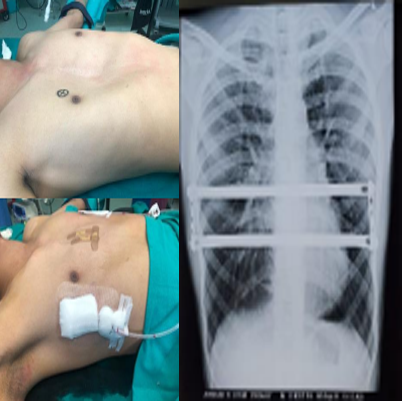

A lung transplant is a surgical process to replace a failing lung with a healthy one. This transplant process is generally done by taking a lung from a dead donor. Moreover, the surgery is reserved for people that have tried other treatments or drugs, but their condition has not bettered enough.

A lung transplant is a surgical process in which a damaged lung is replaced with a healthy lung. This surgery is for those patients that suffer from serious chest ailment. Other than this, when other treatments and medicines fail to work, the surgeon might suggest a lung treatment. This is highly required for patients that rely on oxygen and those that suffer from serious lung issues and might die in the next 4-8 months.